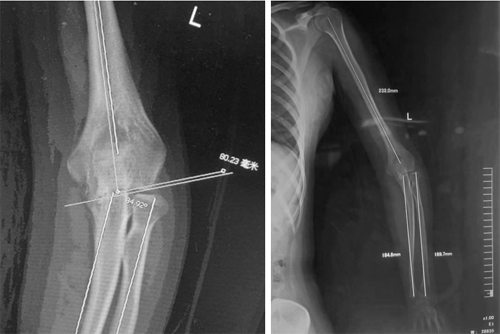

术前测量

术前,蒋协远教授带领团队反复进行了影像学测量,敏锐地发现患者的内翻畸形主要来源于尺骨侧,并非常见的肱骨侧,这给团队出了大难题。肘内翻畸形常见于儿童髁上骨折患者,畸形多来源于肱骨侧,通常采用肱骨髁上截骨内固定术治疗。然而该患者畸形来源于关节的内翻和尺骨的畸形,肱骨远端外翻角度正常,采用传统的肱骨髁上截骨无法解决患者的问题。蒋协远教授结合治疗陈旧性孟氏损伤的治疗经验大胆地提出采用尺骨截骨内固定术治疗患者特殊类型的肘内翻畸形。

术后肘关节正侧位X线片显示尺骨畸形矫正,内固定位置良好